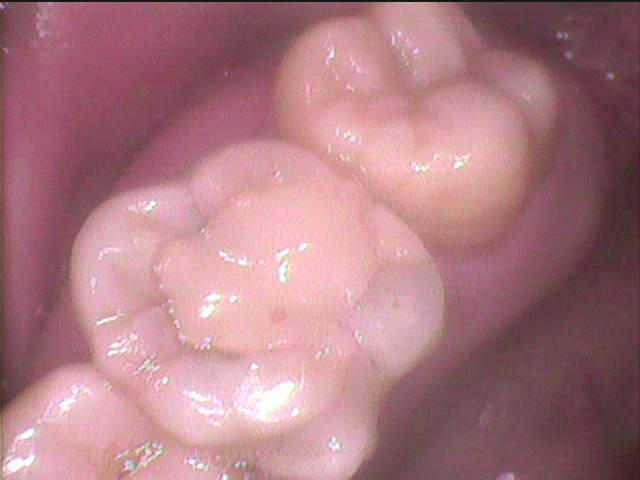

手前の歯との間から虫歯が中心に向かっているのが

よくわかります。

アクセスオープニング。

根管処置の基本的スタート